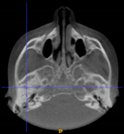

Three points determined the Acta plane: O, F right (FR), and F left (FL) (Table 2). Point O is the midpoint between the most craniodorsal point of the dorsum Sella and the most posterior dorsal point of the Basion in the midsagittal plane (Figure 1). Both points F are a result of the intersection between two lines: the line that connects the most inferior points of the lower orbital margins, right and left, and a line perpendicular to this line that runs through the most external points of the orbital margins, right and left (Figure 2). The new transverse reference plane, the Acta plane (Figure 2), is created by connecting the O-point (Figure 1) with FR and FL (Figure 2).

Point O (green dot) is the midpoint between the dorsum Sella (Se) (red dot) and the Basion point (Ba) (yellow dot).

(A) Construction of the F-points (right and left), frontal view. The F-points are originated from the intersection between the line connecting points A (the most inferior point of the lower orbit) and the perpendicular line to it that passes through points B (most external/lateral point of the Orbita). (B) Transverse view of the ACTA plane.